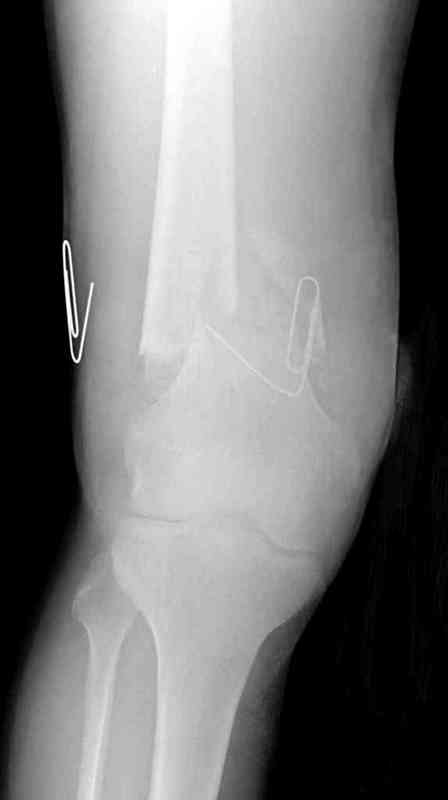

Вчера утром поступил больной с огнестрельной раной, осмотрен сосудистым специалистом, сделана ангиограмма (снимки) Во время операции при вскрытии обнаружили кровотечение, рану забили салфетками, установили пластину locking DePuy.

Из-за возрастающего давления в компартменте сделана фасциотомия и вызванный сосудистый хирург ушил разрыв вены на уровне перелома. Все раны оставлены открытими, в пятницу закроем.